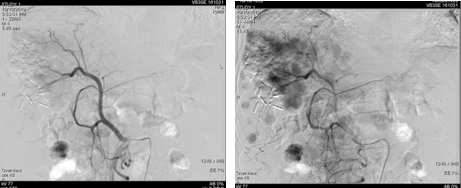

遂继续以碘油4 ml+0.9%氯化钠20 ml+吡柔比星20 mg+雷替曲塞2支方案,行第二次TACE治疗。

图片

图:第二次TACE治疗

为进一步抑制肿瘤进展,经多学科团队(MDT)讨论,予患者我国自主研发的抗血管生成药物联合PD-1单抗进行治疗。2019年8月19日复查,肝增强CT示,肝右叶占位性病变介入术后改变,其内异常强化,考虑肿瘤存活或复发,考虑肝右叶后段原发性肝癌。再次行TACE治疗。